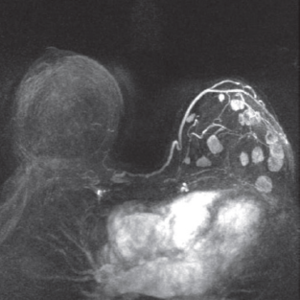

Breast cancer screening and presurgical diagnosis are currently based on mammography, ultrasound and more sensitive imaging technologies; however, noninvasive biomarkers represent both a challenge and an opportunity for early detection of cancer.